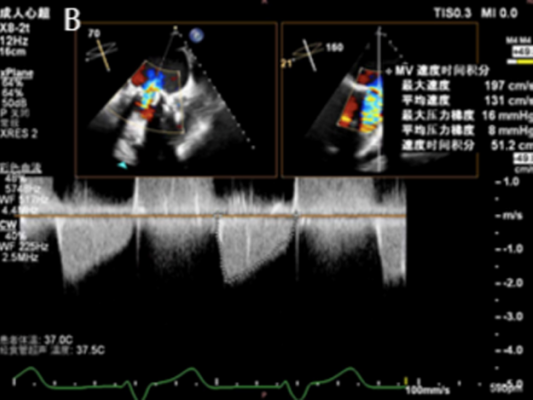

该患者为83岁男性,11年前植入的主动脉瓣(圣犹达医疗21mm)和二尖瓣(圣犹达医疗27mm)生物假体退化,导致充血性心力衰竭,左心室射血分数(LVEF)为40%,合并重度主动脉瓣狭窄/关闭不全及重度二尖瓣关闭不全。症状包括不明原因的胸闷、喘息、端坐呼吸和持续的夜间阵发性呼吸困难。检查发现心律失常、频繁早搏,二尖瓣/主动脉瓣区可闻及4/6级收缩期杂音。经胸/经食道超声心动图(TTE/TEE)确认二尖瓣生物假体重度反流[缩流宽度(VCW)8mm,平均跨瓣压差8mmHg],主动脉瓣生物假体重度狭窄/反流(平均跨瓣压差44mmHg;峰值流速5.7m/s,缩流宽度8mm)(图1)。其他检查发现左心房明显扩大,LVEF40%,中度肺动脉高压(估测收缩压57mmHg)。冠状动脉造影未见明显异常。术前心脏计算机断层扫描测量主动脉瓣环尺寸为周长58.6mm,面积252.9mm²,直径18.1mm,并发现右冠状动脉高度偏低(6.4mm)。二尖瓣瓣环直径24mm,主动脉-二尖瓣角度为61.8°,计算新左心室流出道面积为999.9mm²,提示经导管二尖瓣瓣中瓣(TMViV)术后左心室流出道梗阻风险较低。NT-proBNP显著升高(11363.03pg/mL)。由于患者高龄、既往胸骨切开术和合并症,传统再次主动脉瓣置换(AVR)或二尖瓣置换(MVR)风险过高。多学科团队在获得患者知情同意后,决定采用ScienCrown自膨式瓣膜同期进行经心尖主动脉瓣瓣中瓣(TAViV)及二尖瓣瓣中瓣(TMViV)植入术。

图1. 生物瓣膜假体功能的超声心动图评估。A:主动脉瓣生物假体严重狭窄伴反流(平均压差44mmHg;峰值流速5.7m/s ,VCW 8mm )。B:二尖瓣生物假体严重反流(VCW 8mm ,平均压差8mmHg)。